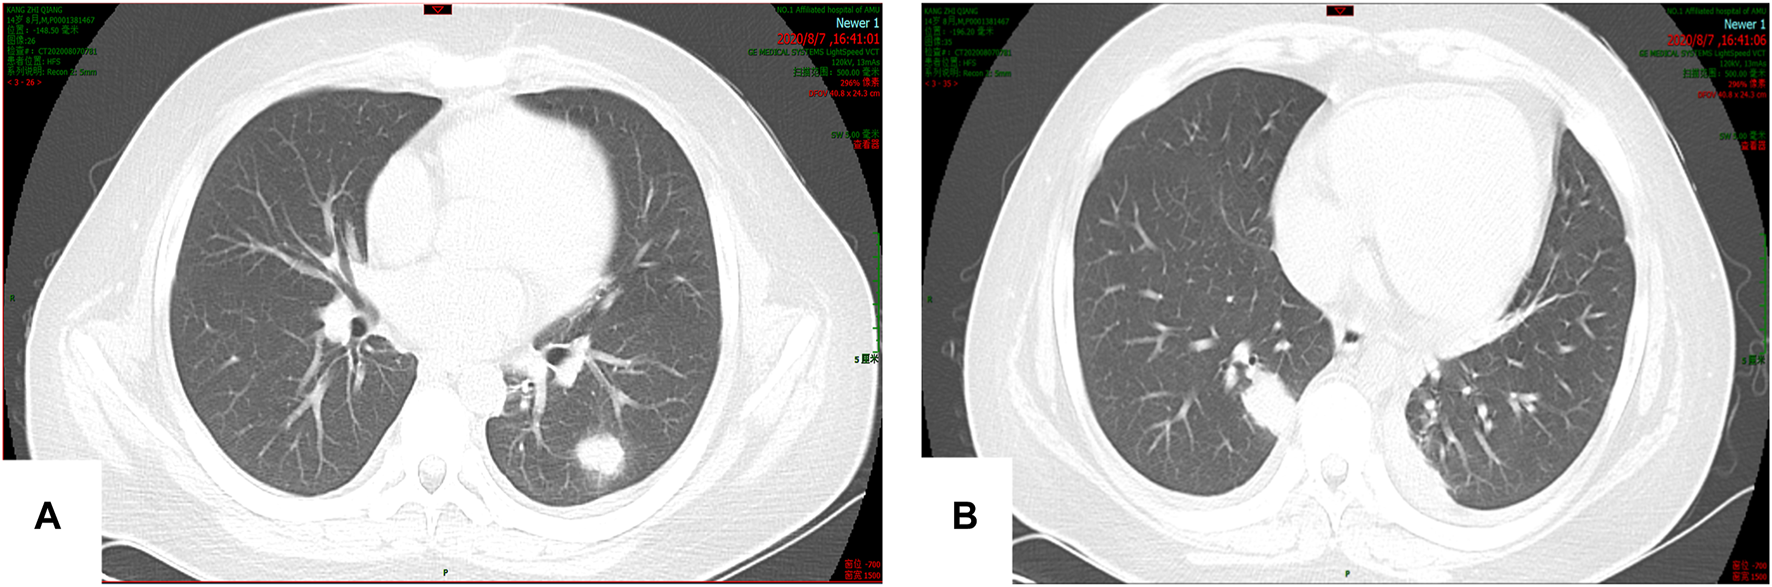

On 7 August 2020, the patient experienced sudden chills, shivering, and hyperpyrexia. Sputum culture revealed Candida albicans, and chest computed tomography (CT) showed multiple nodules in the lungs (Figures 2A,B). The 1,3-β-D glucan test (G test) and galactomannan antigen detection test (GM test) were negative. Due to poor coagulation, tracheoscopy was not performed. Pulmonary candidiasis was diagnosed, and the patient’s fever persisted after a week of treatment with fluconazole 400 mg/d ivgtt. A repeat sputum culture on 14 August 2020 revealed Aspergillus niger, resulting in a diagnosis of invasive pulmonary aspergillosis (IPA). Fluconazole was changed to voriconazole (loading dose on 18 August 2020 of 400 mg q12 h ivgtt, and maintenance dose of 200 mg q12 h ivgtt was started on D2. The regimen was adjusted according to the clinical situation and therapeutic drug monitoring (TDM) results), and his condition improved.

FIGURE 2. (A,B) Multiple nodular soft tissue shadows were observed in both lungs. The larger one was located in the lower lobe of the right lung (15 × 23 mm).